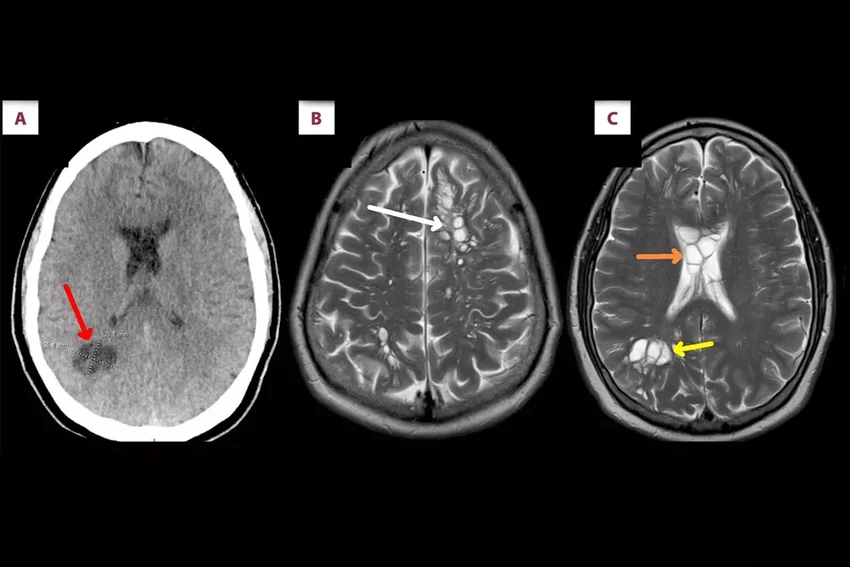

Компьютерная томография головы показала шокирующую картину: в мозге, с обеих сторон, обнаружились множественные кисты. Последующий анализ поставил точный диагноз: нейроцистицеркоз. Это особая и очень опасная форма заражения личинками свиного цепня (Taenia solium). Представьте: ваш собственный мозг становится инкубатором для паразита.

Пациенту прописали курс противопаразитных и противовоспалительных препаратов. Лечение дало результат: очаги поражения в мозге значительно уменьшились, а изматывающие головные боли наконец отступили. Эта история — мощное напоминание о том, что даже в развитом мире простые правила безопасности на кухне и в быту могут уберечь от невероятных рисков.